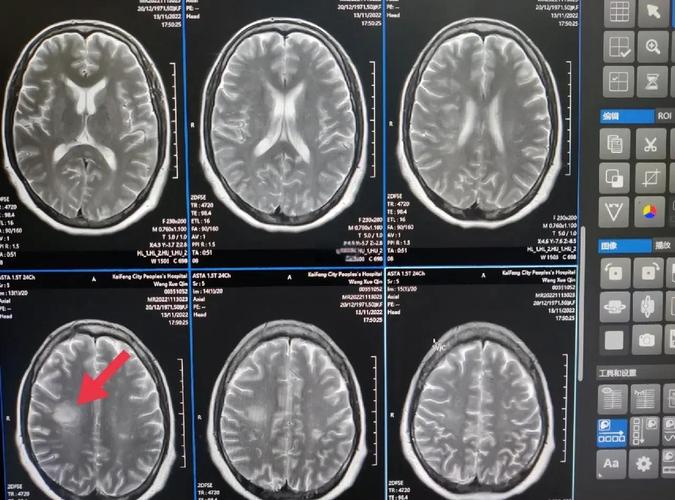

常规的CT检查在发病6小时内,对早期脑梗死的检出率很低(可能低于20%),而特定的磁共振检查(特别是DWI序列)在发病数分钟到数小时内,就能非常敏感地发现脑梗死的早期迹象,检出率可高达90%以上。

对于怀疑急性脑梗死的患者,MRI是比CT更早期、更敏感的检查手段。

- 表现: 在DWI图像上,这种“水分子扩散受限”的区域会显示为明显的高信号(亮白色),这个改变在脑缺血发生后的几分钟内就可能开始出现,并且在发病后30分钟到1小时内,诊断的敏感性和特异性就非常高了。